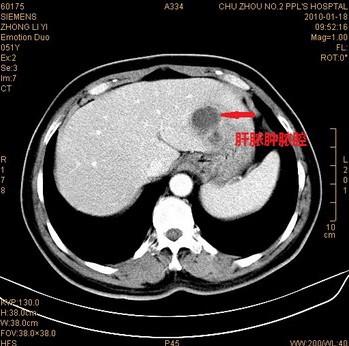

x线透视下发现有肝区阴影增大,右侧膈肌抬高,呼吸时膈肌活动范围受限的病人,结合临床表现应警惕细菌性肝脓肿,应进一步做B超、CT、MRI等影像学检查。B超、CT与MRI检查均能显示肝脏有单发或多发的低密度影,结合临床表现均能确诊。在目前诸多的辅助检查中,B超是首选的检查方法,B超检查可分辨肝内直径2cm的脓肿病灶,可以明确脓肿的多少、部位和大小,操作简便、安全、方便,且可以随时重复检查,必要时可在B超引导下进行穿刺,穿刺抽出脓液即可明确诊断又可进行细菌培养、药敏实验,选择有效抗菌药物。

根据病史,临床表现,以及B超和X线检查,即可诊断本病。必要时可在肝区压痛最剧烈处或超声引导下行诊断学穿刺,抽出脓液即可证实本病。